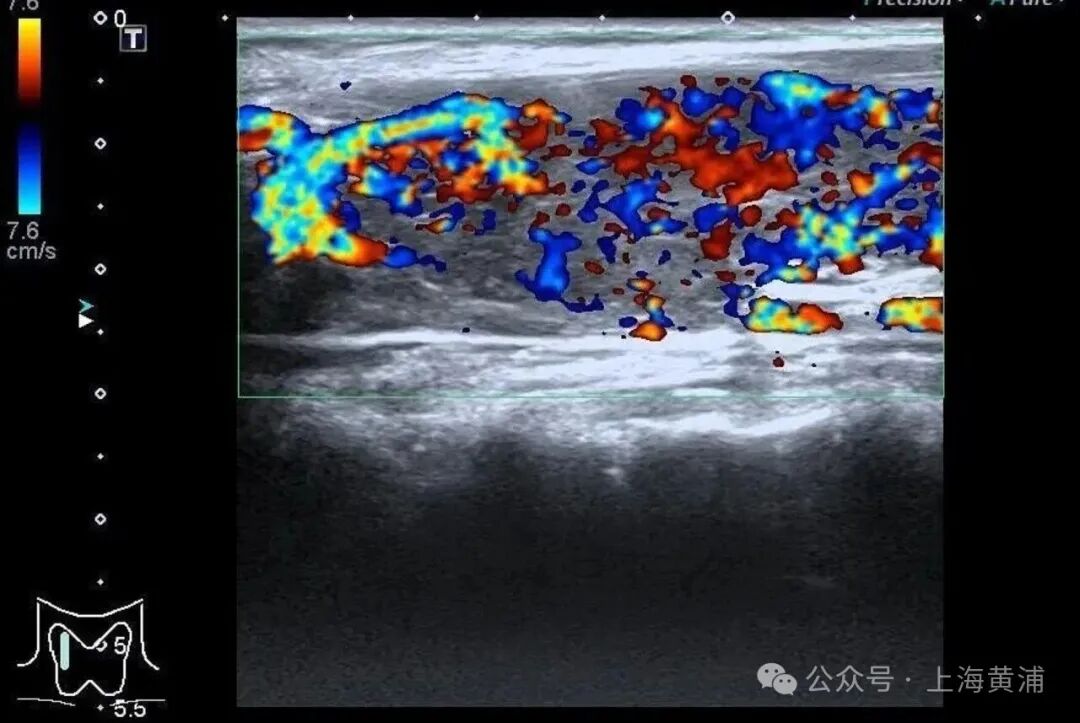

入院后的检查结果显示

陈女士的身体

正被一场“激素风暴”席卷

甲状腺功能检查中,游离T3高达20.83 pmol/L(正常值3.5 - 6.5pmol/L),游离T4高达88.42 pmol/L(正常值11.5 - 22.7pmol/L),这两项核心激素都超过正常上限数倍,而本应调控它们的促甲状腺激素(TSH)却几乎测不出来,这明确证实了陈女士患有极其严重的甲状腺毒症。心脏超声结果同样不容乐观,射血分数仅有40%(正常应高于55%),这意味着心脏泵血能力大幅下降。

同时,CT检查发现她的双侧胸腔、腹腔存在积液。综合各项检查结果,医生判断陈女士患上了甲状腺危象,这是甲亢最凶险的并发症。